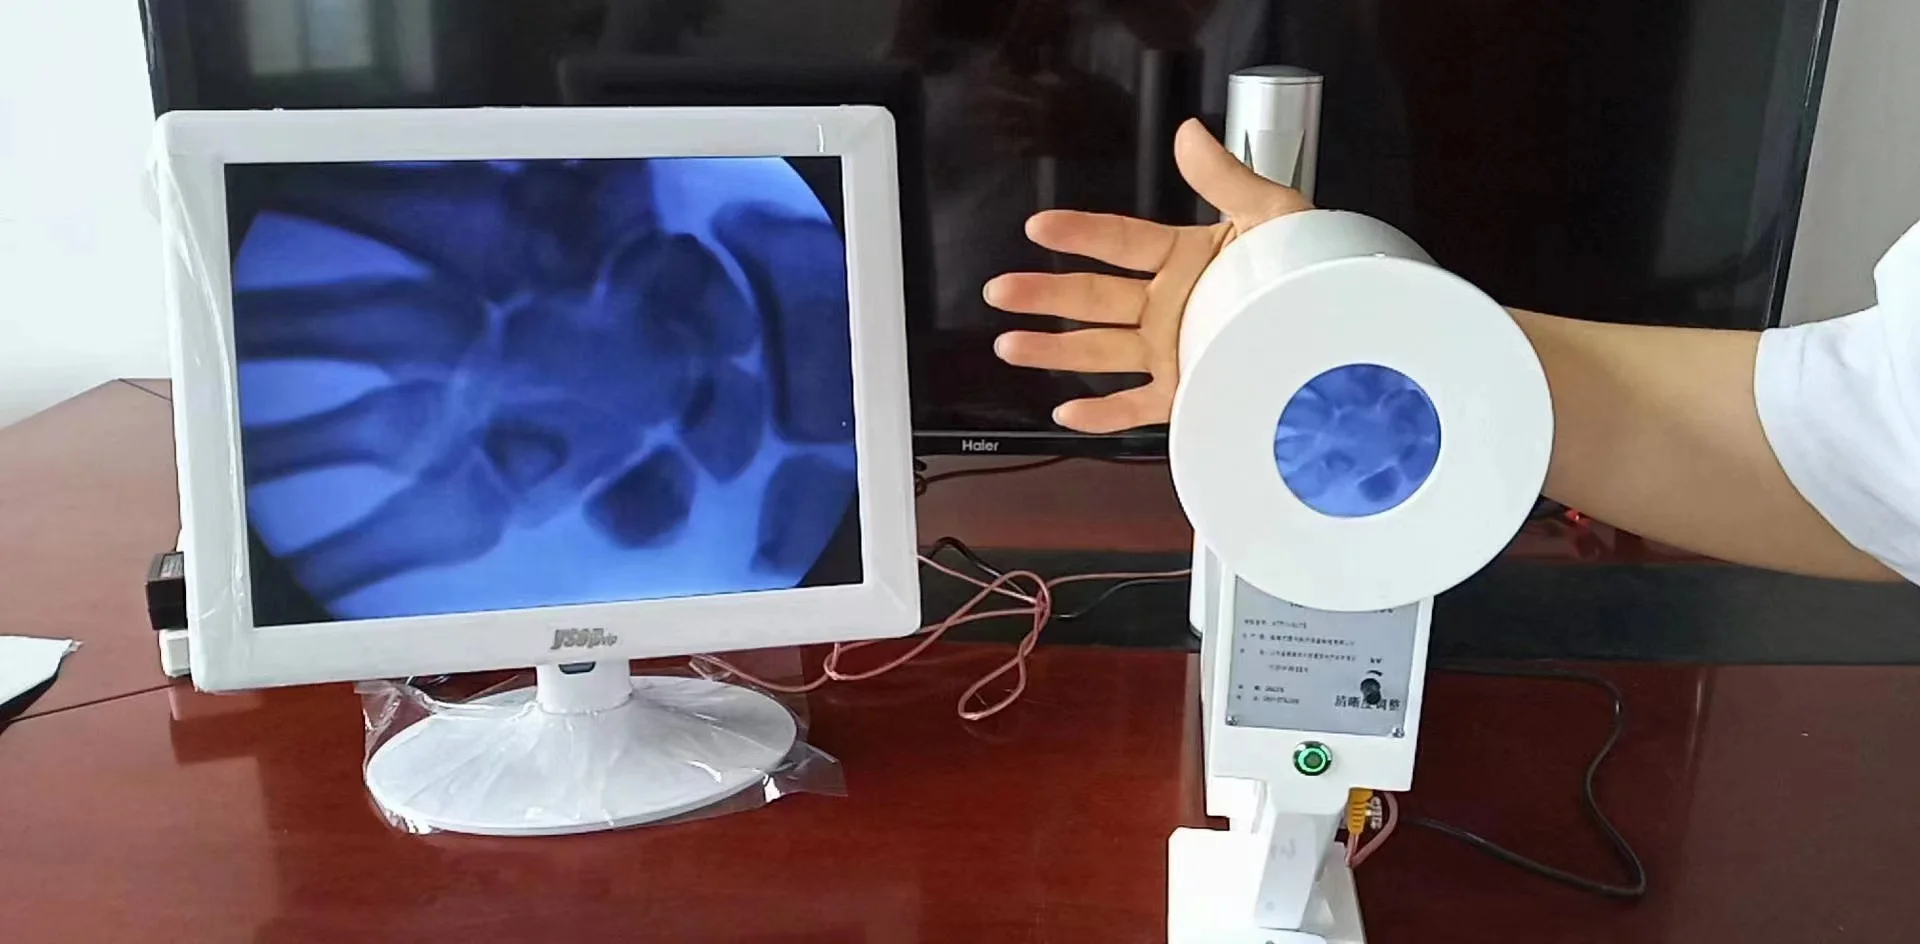

Организация рабочего пространства: стенды для рентгеновских снимков